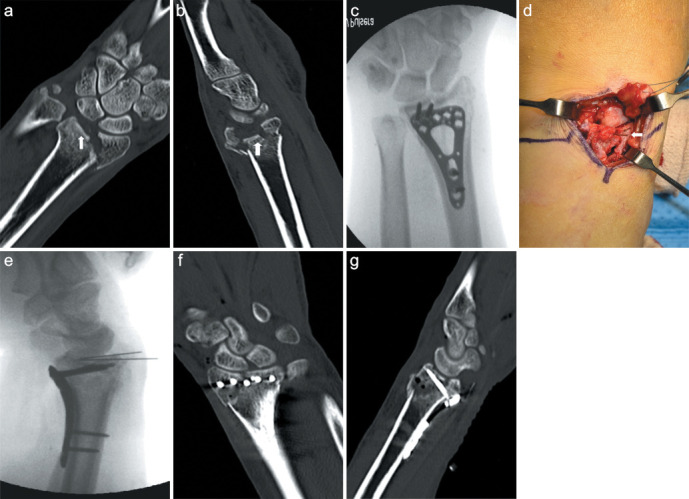

Methods: Thirty patients who underwent dorsal plating (Group A) (14 females, 16 males; mean age = 56.8 ± 10.1 years) and 28 who underwent volar plating with limited dorsal open reduction (Group B) (12 females, 16 males; mean age = 55.6 ± 17.7 years) for type C3 distal radius fractures with impacted articular fragments between 2006 and 2019 were retrospectively analyzed. The mean follow-up was 14.5 ± 3.2 months in group A and 13.2 ± 2.4 months in group B. The articular step-off, articular gap and joint penetration by screws on the computed tomography scans were used for radiologic evaluation. The functional outcomes were evaluated with range of motion, grip power, Quick Disabilities of the Arm, Shoulder, and Hand (DASH) score, and Mayo wrist score.

Results: No significant difference was found in the step-off distance at 1 year after surgery between the two groups (P < 0.05). The ranges of extension, rotation, and radial and ulnar deviations did not differ between the groups. However, group B had a significantly higher range of flexion in the wrist joint than Group A (P = 0.010). The grip power, DASH score, and Mayo wrist score did not also differ between the groups. Implant removal owing to any discomfort at the operative site was performed in 15 patients (63%) in Group A and 7 patients (28%) in Group B.

Conclusion: Similar clinical results can be obtained by both dorsal plating and volar plating with limited dorsal open reduction in treating type C3 distal radius fractures with impacted articular fragments. However, volar plating with limited dorsal open reduction can provide better wrist flexion with a low incidence of complications associated with implantation.